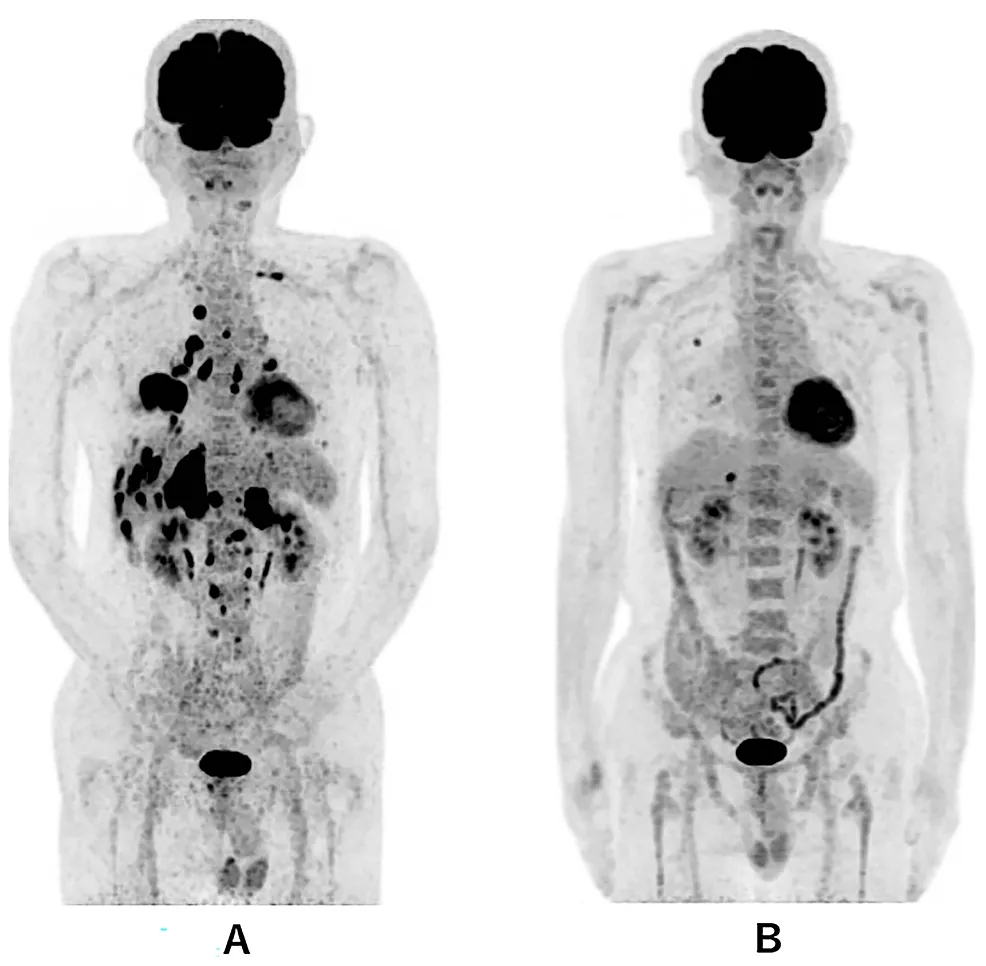

3.诊断时PET-CT显示除右下肺原发肿瘤外,还显示双侧多发肺内转移、多发肝转移、双侧肾上腺转移和多发骨转移(图A)。第 479 天的全身 PET-CT,显示右肺有两个小转移灶,肝脏有一个小转移灶(图B)。

图1 全身PET-CT对比

答:诊断时PET-CT显示除右下肺原发肿瘤外,还显示双侧多发肺内转移、多发肝转移、双侧肾上腺转移和多发骨转移。B:第 479 天的全身 PET-CT,显示右肺有两个小转移灶,肝脏有一个小转移灶。